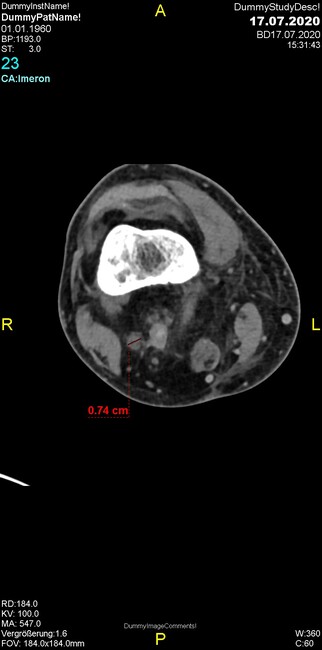

Um welche Modalitäten handelt es sich?

- Röntgen p.a. und lateral, CT coronar Knochenfenster, CT axial Weichgewebsfenster

- Röntgen p.a. und oblique, CT coronar Knochenfenster, CT axial Weichgewebsfenster

- Röntgen p.a. und lateral, CT sagittal Weichgewebsfenster, CT coronar Knochenfenster

- Röntgen p.a. und oblique, CT sagittal Knochenfenster, CT coronar Weichgewebsfenster

- Röntgen p.a. und lateral, CT coronar Weichgewebsfenster, MR axial

Was fällt in der CT im Knochenfenster auf?

- Weichgewebskalzifikationen lateral angrenzend an den Gelenkspalt